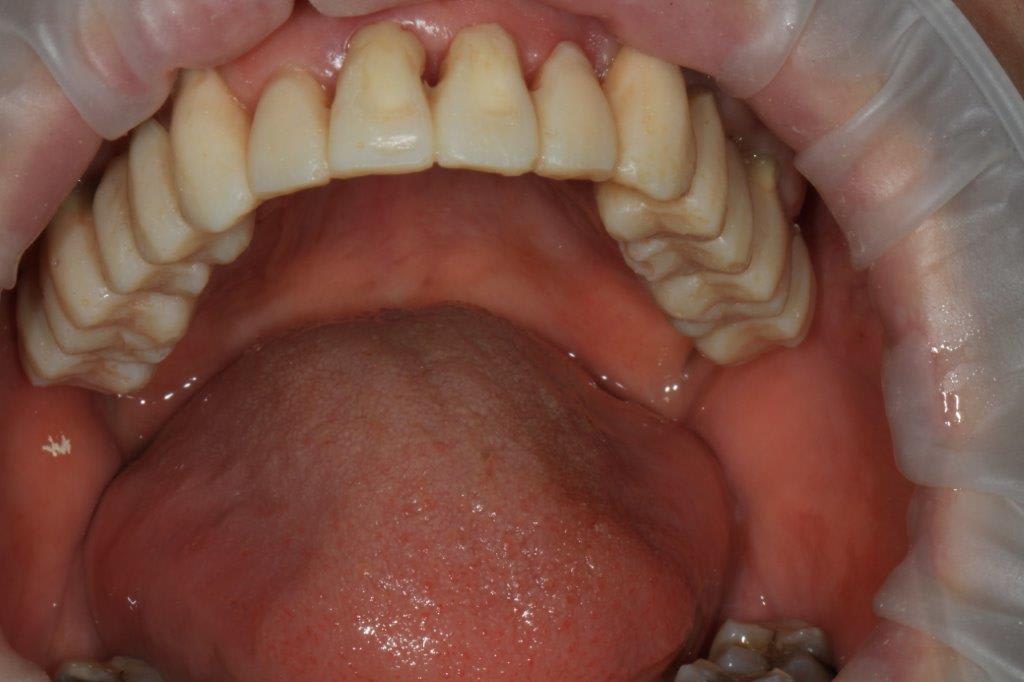

modèles de départ, photos avec le téléphone, désolé, mais ça donne une petite idée

--

xbk

La connaissance s'acquiert par l'expérience, tout le reste n'est que de l'information." ALBERT EINSTEIN